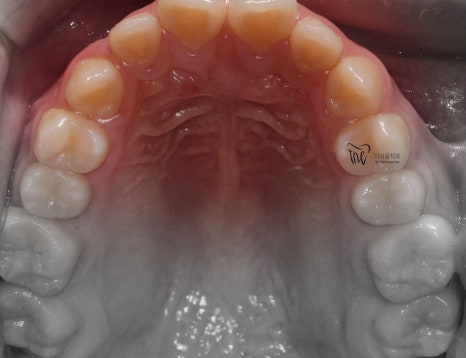

근데 또 교합면에서 보면, 악궁의 형태 자체는

그렇게 나쁜 편은 아닙니다. 다만, 회전이 되어있는

일부 치아들 및 치간이개의 현상 이외에는

별다른 특이사항을 볼 수 없죠.